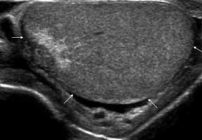

Badanie umożliwia ocenę jąder, najądrzy, osłonek jąder oraz struktur znajdujących się w obrębie worka mosznowego. Pozwala także wykryć obecność żylaków powrózka nasiennego, które mogą mieć znaczenie kliniczne i wpływać na dalsze postępowanie diagnostyczne lub lecznicze.

USG jąder jest jednym z podstawowych badań obrazowych wykorzystywanych w diagnostyce zmian w obrębie moszny. Dzięki niemu lekarz może lepiej ocenić przyczynę dolegliwości i zdecydować o dalszych krokach.